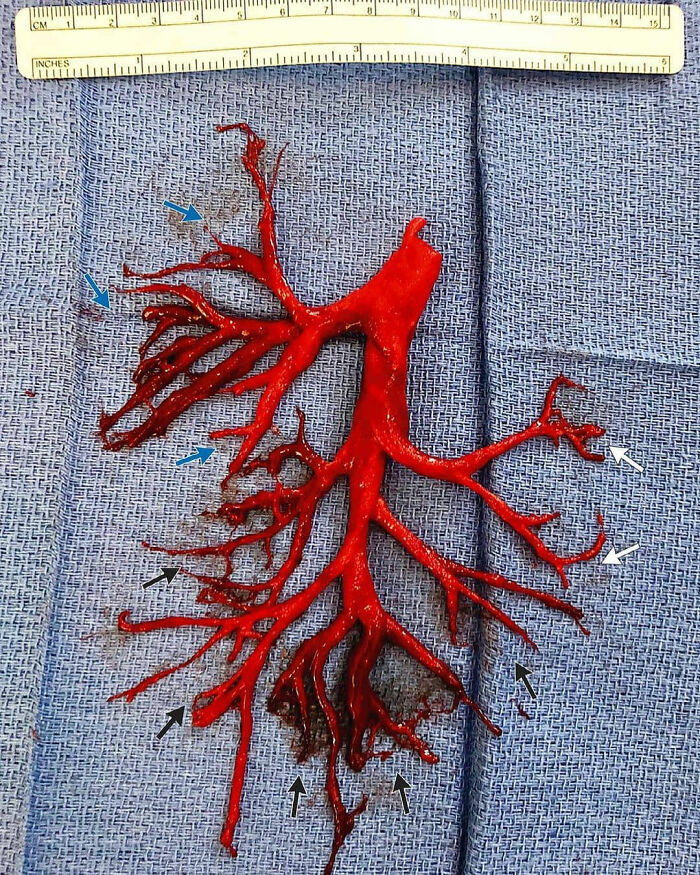

A Blood Clot Coughed Up By A Patient, That Perfectly Shaped The Lung’s Cavity It Filled

This huge blood clot took the shape of the bronchial tree. This photo shows the most visually arresting medical anomalies. The image is of a mysterious, branchlike structure that, posted elsewhere, would probably pass for a cherry-red chunk of some underground root system or a piece of bright reef coral. But this is no creature of the deep. It’s a completely intact, six-inch-wide clot of human blood in the exact shape of the right bronchial tree, one of the two key tubular networks that ferry air to and from the lungs. And it was coughed up in one piece. This cast was produced by a 36-year-old man who was admitted to the intensive care unit with an acute exacerbation of chronic heart failure. His medical history included heart failure with an ejection fraction of 20%, bioprosthetic aortic-valve replacement for bicuspid aortic stenosis, endovascular stenting of an aortic aneurysm, and placement of a permanent pacemaker for complete heart block. An Impella ventricular assist device was placed for management of acute heart failure, and a continuous heparin infusion was initiated for systemic anticoagulation. During the next week, the patient had episodes of small-volume hemoptysis and increasing respiratory distress. During an extreme bout of coughing, the patient spontaneously expectorated an intact cast of the right bronchial tree. Terrifying as it is, it's a fascinating illustration of the anatomy of the right bronchial tree, which consists of three segmental branches in the upper lobe (blue arrows), two segmental branches in the middle lobe (white arrows), and five segmental branches in the lower lobe (black arrows).